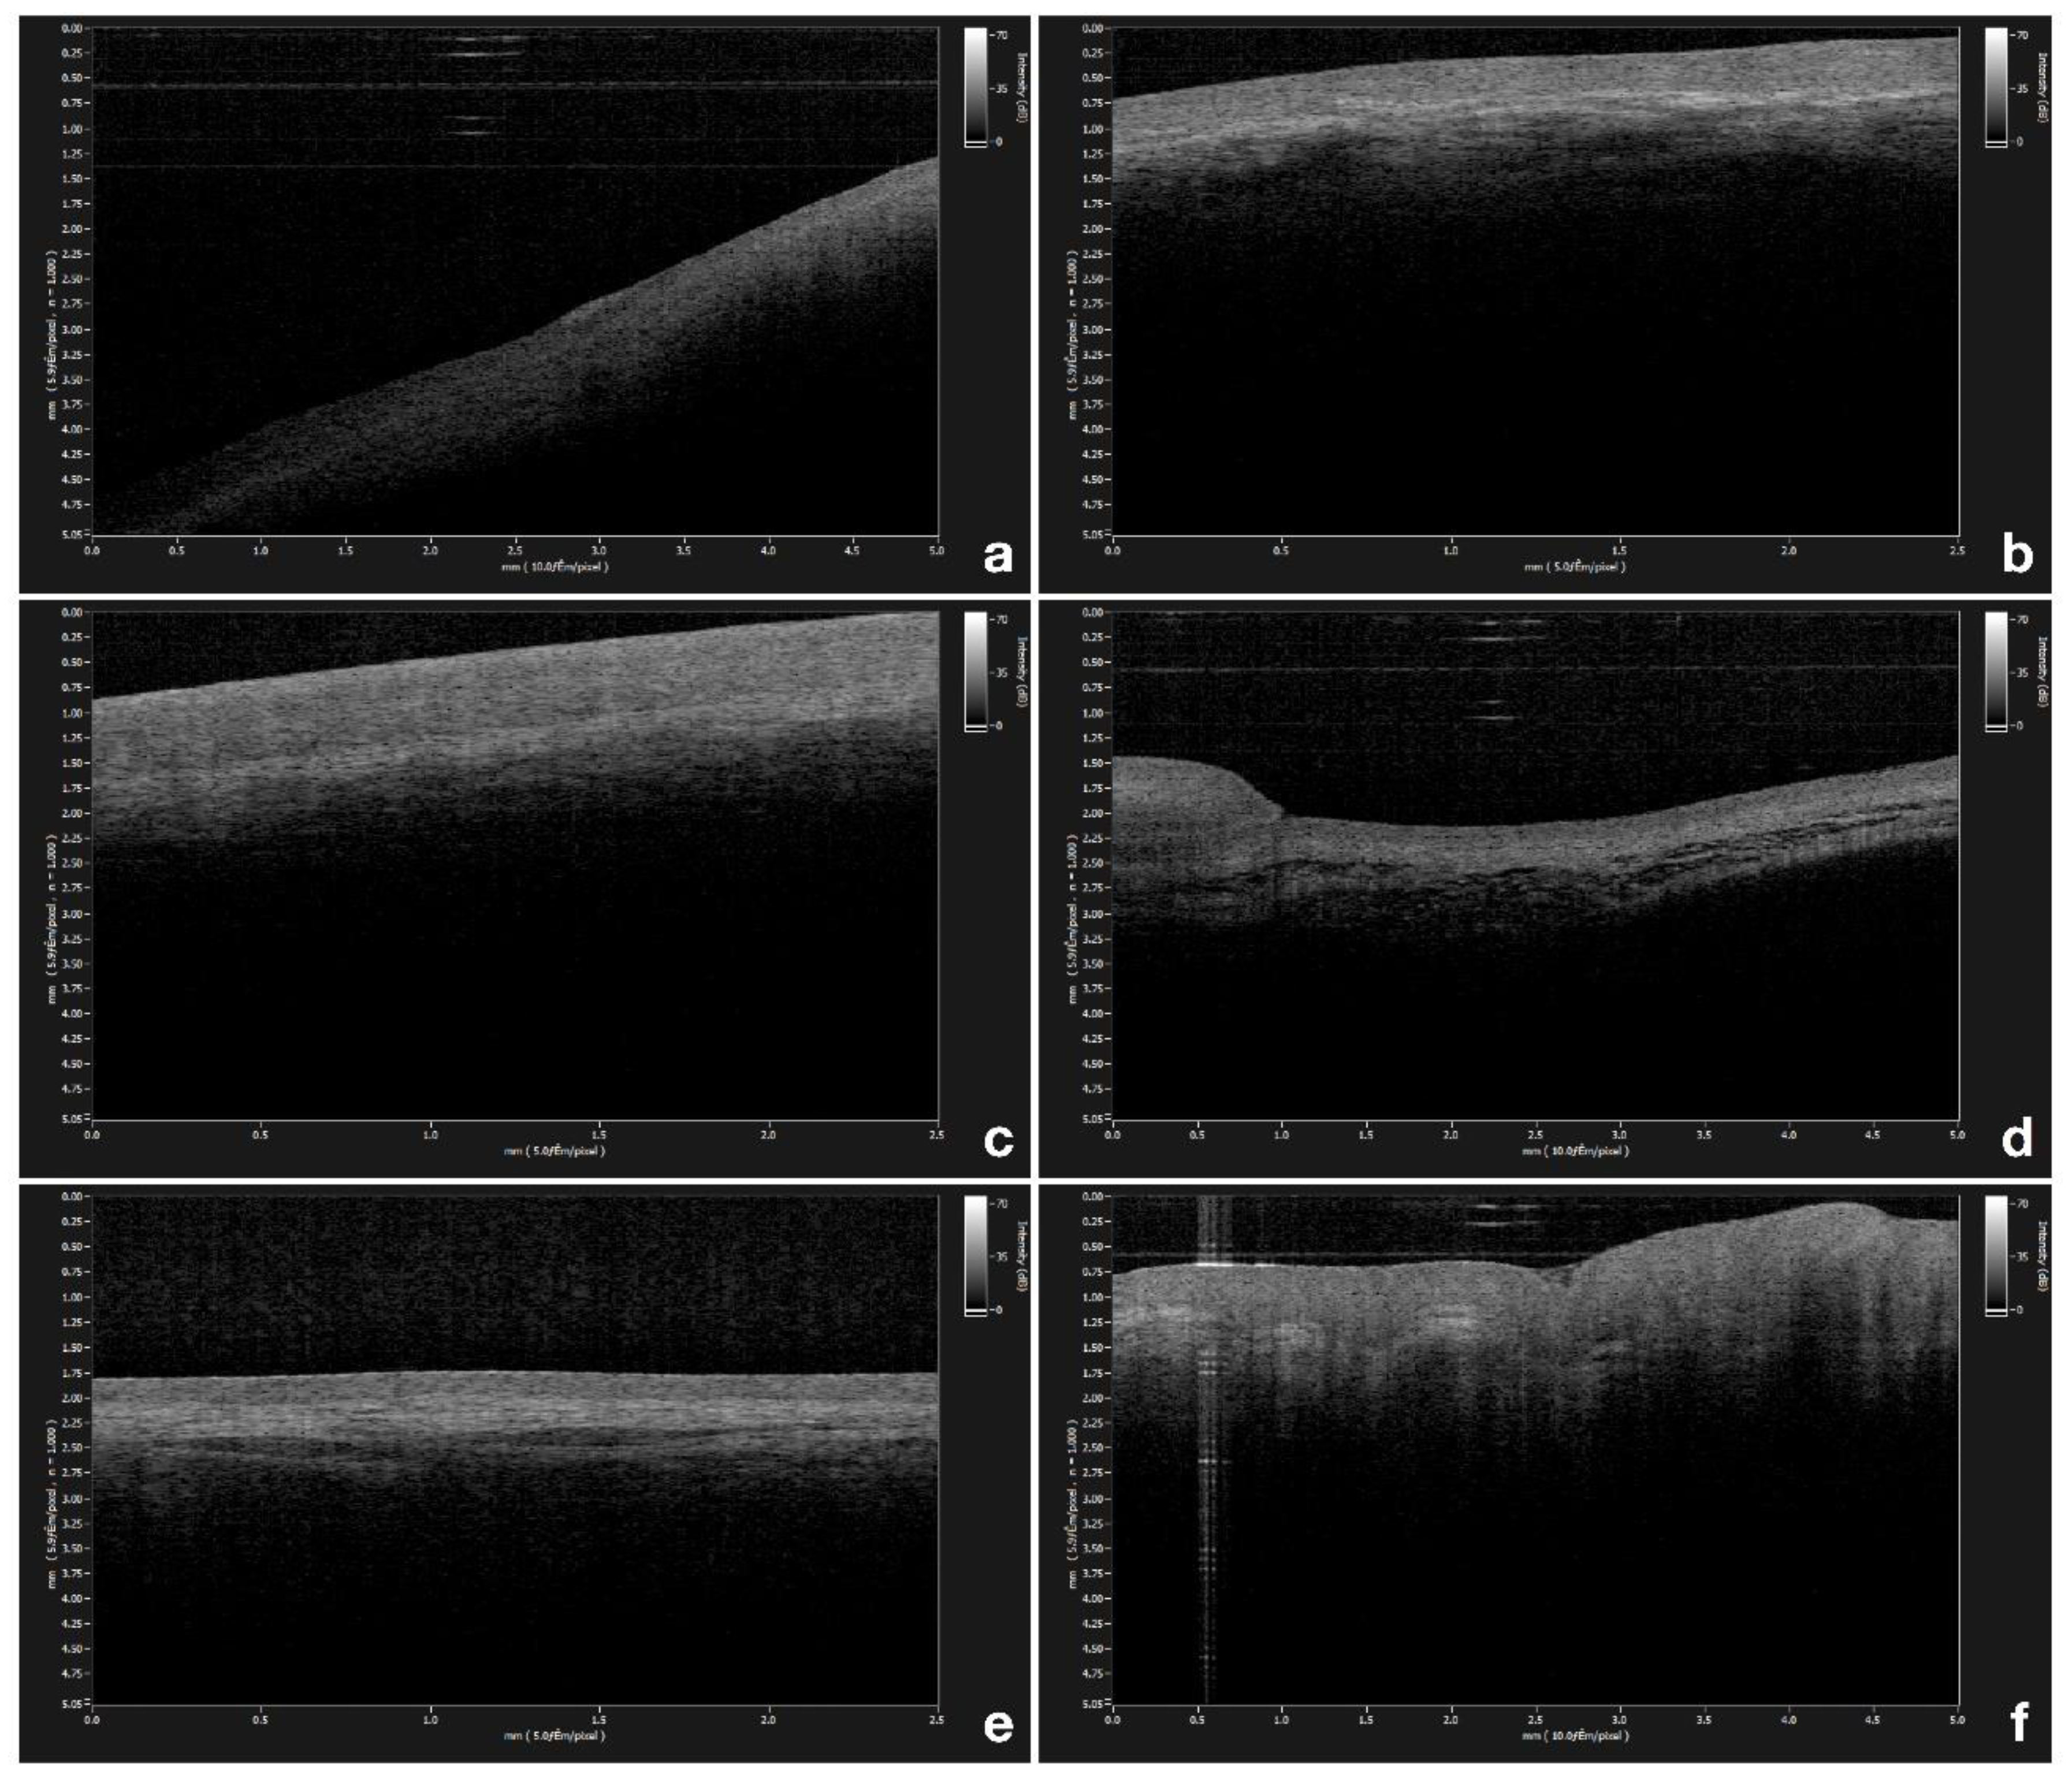

| Anatomic Location | Thickness (µm) | SD | |

|---|---|---|---|

| gingiva | Mean | 285.04 | ± 32.98 |

| Min | 218.30 | ||

| Max | 333.33 | ||

| labial mucosa | Mean | 339.83 | ± 36.44 |

| Min | 271.19 | ||

| Max | 405.56 | ||

| buccal mucosa | Mean | 545.40 | ± 62.45 |

| Min | 373.75 | ||

| Max | 659.79 | ||

| ventral surface of the tongue | Mean | 239.79 | ± 37.30 |

| Min | 159.09 | ||

| Max | 318.00 | ||

| floor of the mouth | Mean | 124.09 | ± 13.53 |

| Min | 100.07 | ||

| Max | 144.44 | ||

| tongue dorsum | Mean | 479.32 | ± 83.56 |

| Min | 333.33 | ||

| Max | 650.02 |